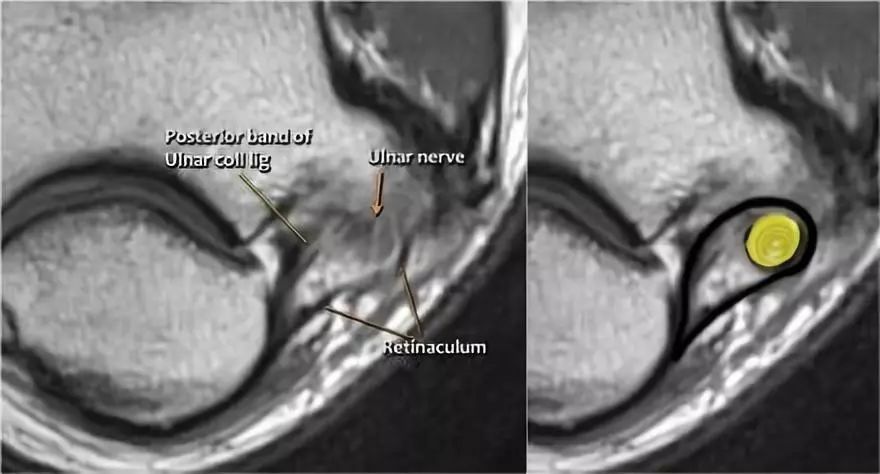

在研究韧带时,尤其是UCL,始终使用轴向图像。如果你看内侧上髁,你会发现后束是一个薄的结构(蓝色箭头)。注意在肘管内的尺神经。

后束形成肘管隧道的地板。支持带覆盖肘管。请注意,前束更厚(白色箭头)。您可以看到前韧带和后韧带之间的区别,即使它们形成一条韧带。走向远端,我们会看到它们合并在一起以附着于崇高的结节。

尺神经:在这里,我们看到了肘管内的尺神经。尺骨侧支带的后带形成隧道的底部,而支持带形成屋顶。

该患者有尺神经神经病变。肘管综合征是一种常见的周围神经病变。它产生于肘管内尺神经,其中该神经传递肘管支持带的下方的压缩。